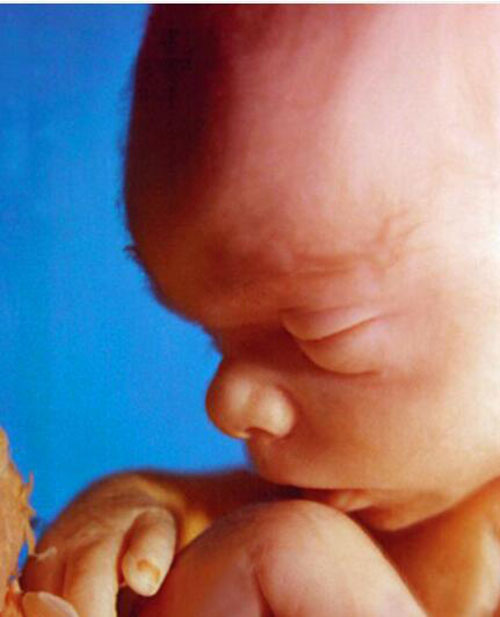

Nhờ công nghệ siêu âm ngày một tiên tiến, các bác sĩ có thể chụp lại những khoảnh khắc không thể chân thực hơn của thai nhi trong bụng mẹ.

Vành tai em bé đã hoàn thiện gần như hoàn toàn, có thể thấy được cả những lông tơ trên da đầu.